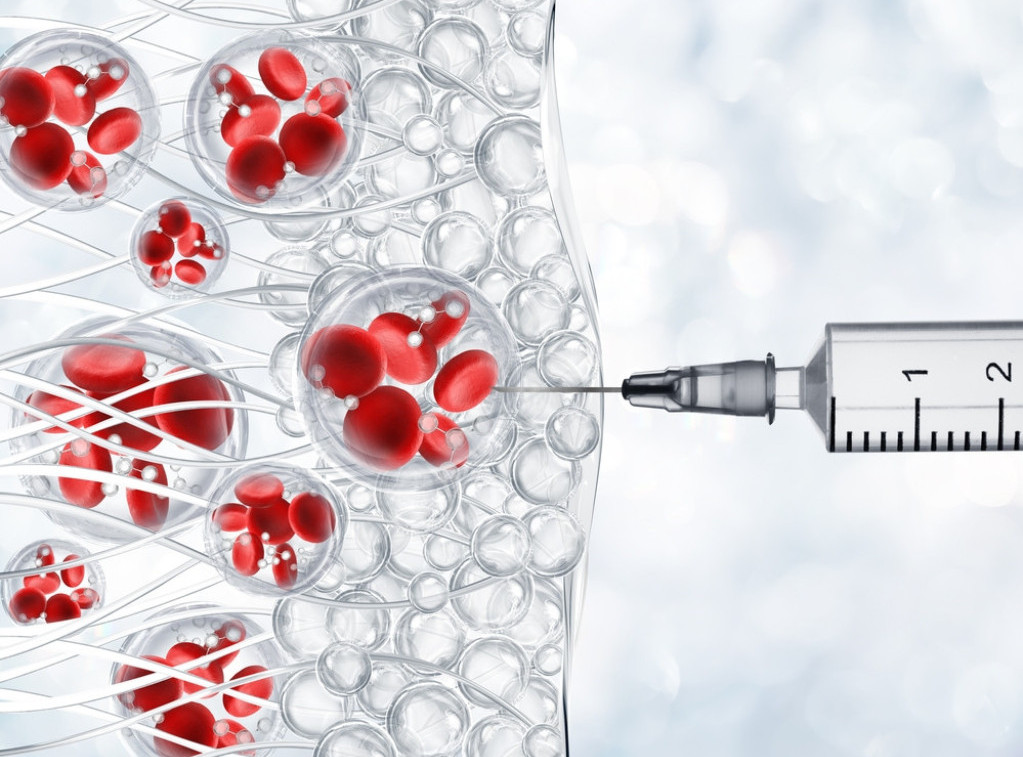

Studija: Nanočestice kao "rezervne baterije" podmlađuju stare i oštećene ćelije